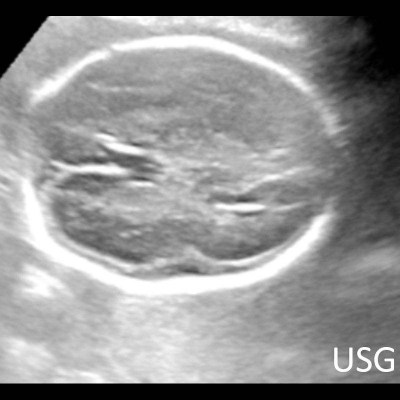

- A) USG incelemede serebral kortikal yapılar düzleşmiş (ok), gyrus sayısı azalmıştır (ok). Kalın ve ekojenik korteks mevcut olup korteks -beyaz cevher ayrımı silik görünümdedir. Posterior fossada ekstraaksiyel BOS mesafesi artmış görünümdedir (ok).

- Gri/beyaz cevher oranı beyaz cevher aleyhine azalmıştır.

- Operkulizasyon yokluğuna bağlı sylvian fissürün açık görünümü ve vertikal yerleşimi karakteristik bir bulgudur. Serebral yapılar; sığ ve vertikal yerleşimli sylvian fissür sebebiyle “8” görünümündedir. Ancak bu görünümün 26. gestasyonel haftaya kadar normal olduğu akılda tutulmalıdır.

- İnsula açıkta olup klastrum ve eksternal kapsül bulunmayabilir. Beynin gross görünümü fetüste sulkusların oluşmaya başladığı 20. gestasyonel haftayla benzer görünümdedir.